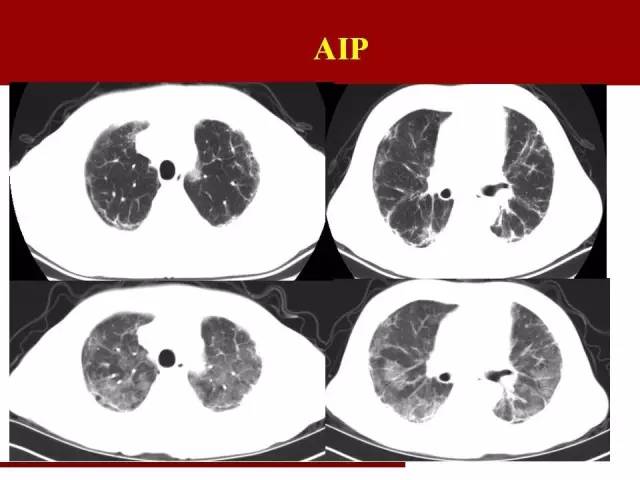

AIP一个特点:快

进展迅速是其特点

在原有的间质性肺炎的基础上迅速进展

这个诊断没有十足把握建议不要轻易下

因为下完之后就几乎判死刑,大部分病人在一个月内死亡